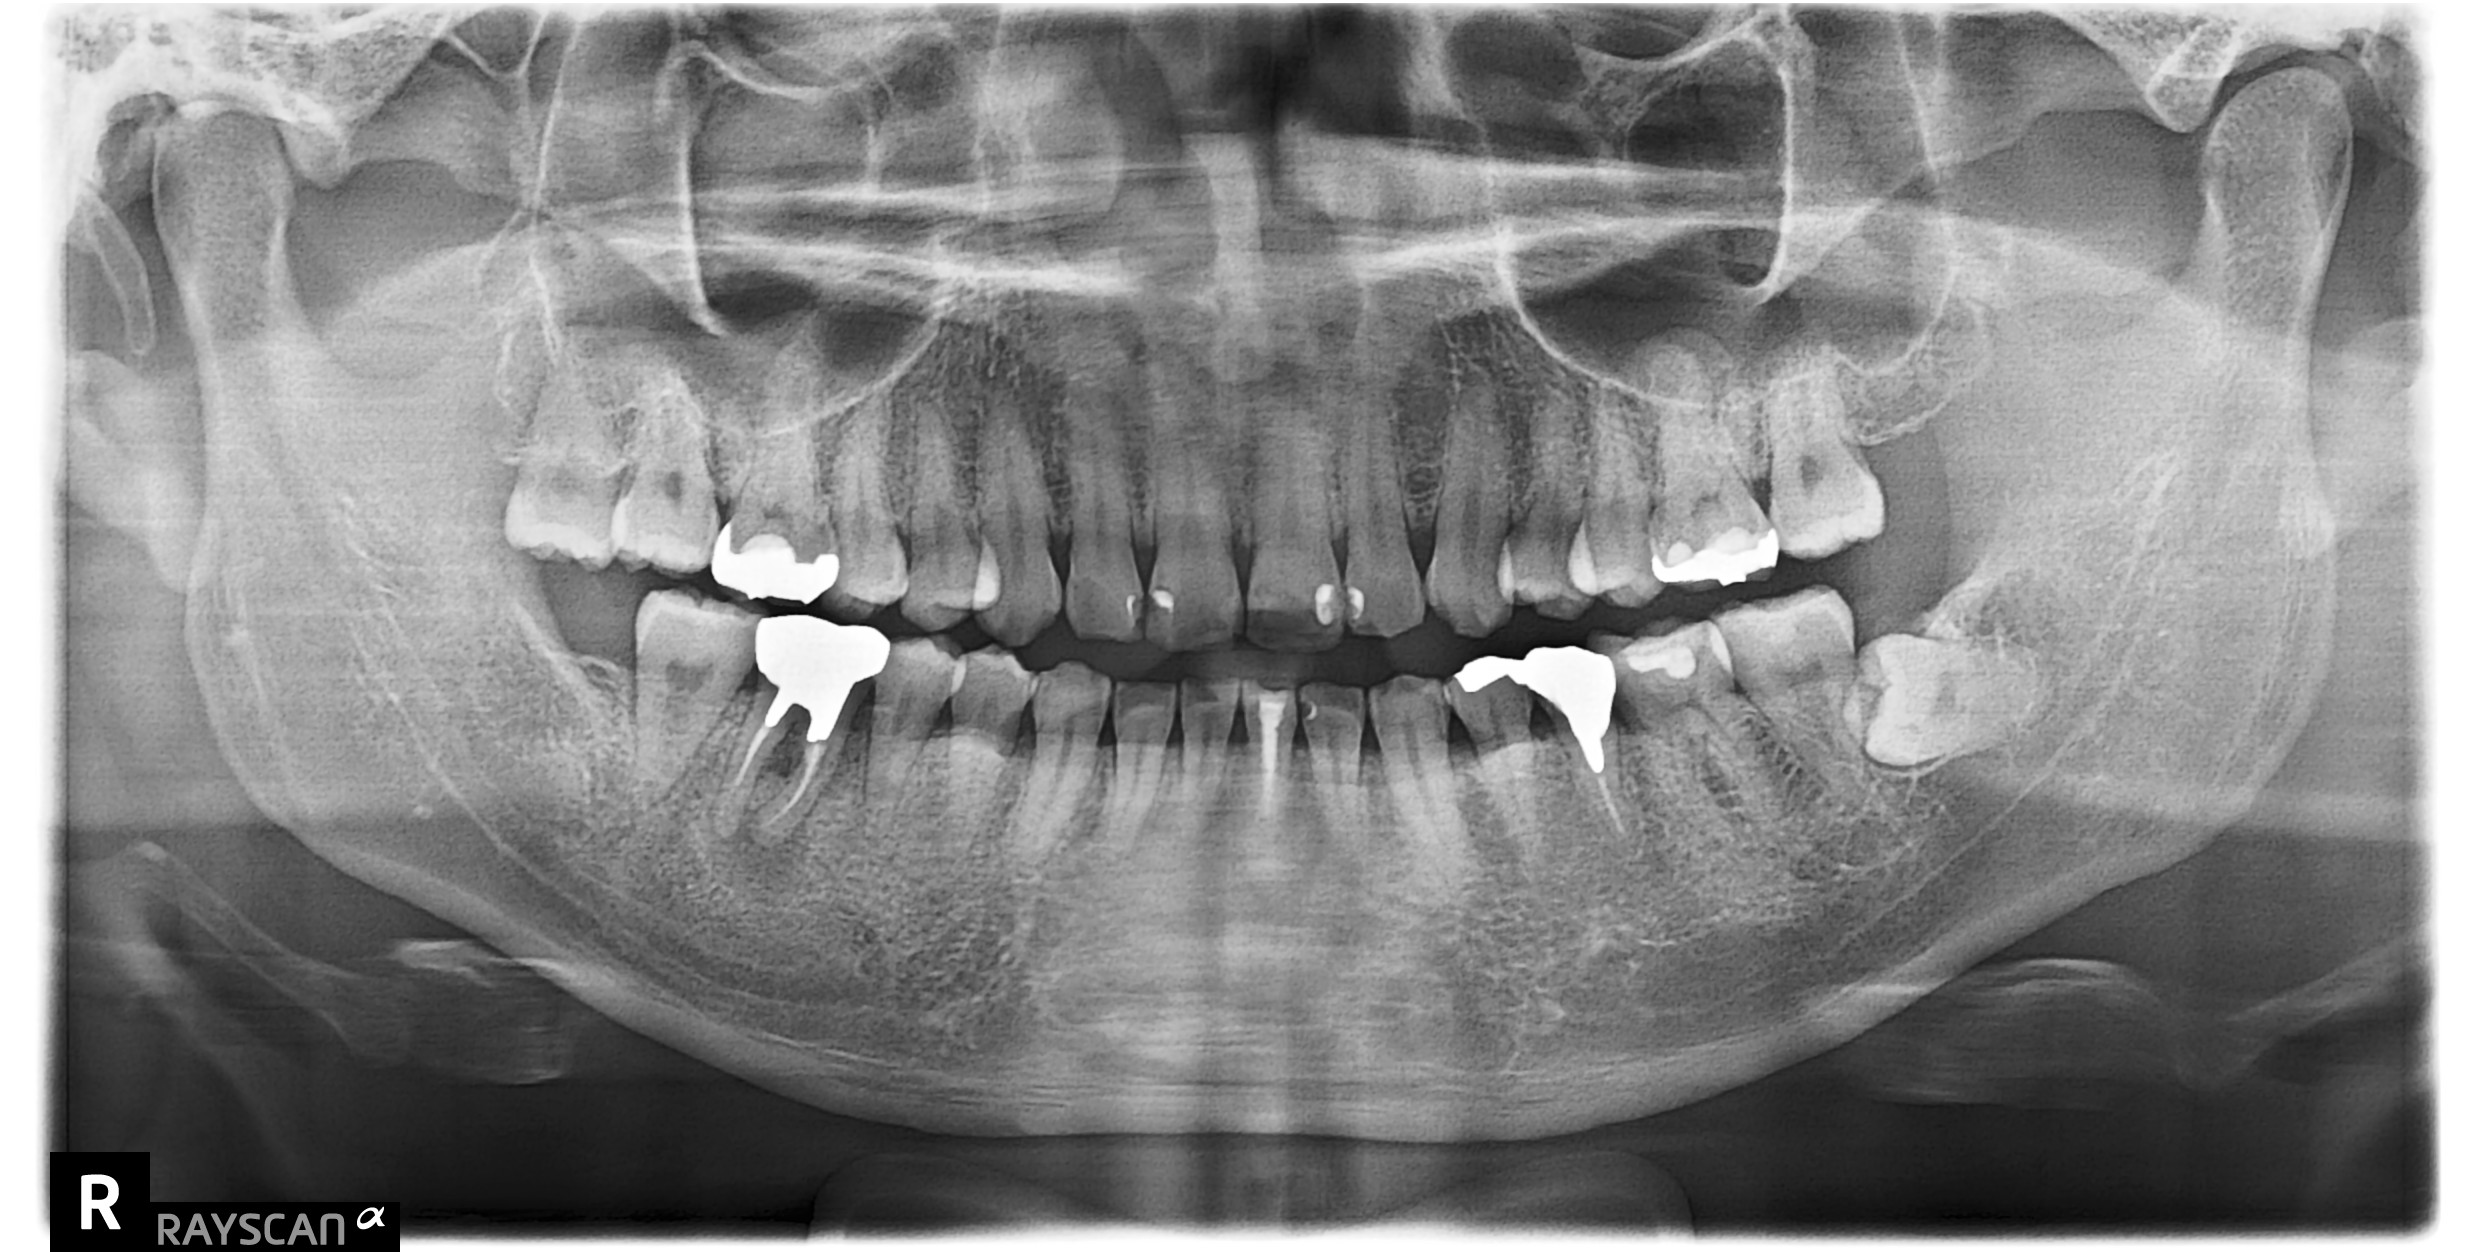

初診時

主訴:右下の歯茎が腫れた

CTで精密検査をすると歯根の中央部で歯周病を起こしており、根の先にも大きな根尖病変を認めました。どちらも病変が大きく、残る歯の量が少なく、隣の歯を削ることが予想されました。通院回数、予後の状態と生活習慣、治療費用、周囲の歯の保護を考え、親知らずの移植をご提案いたしました。